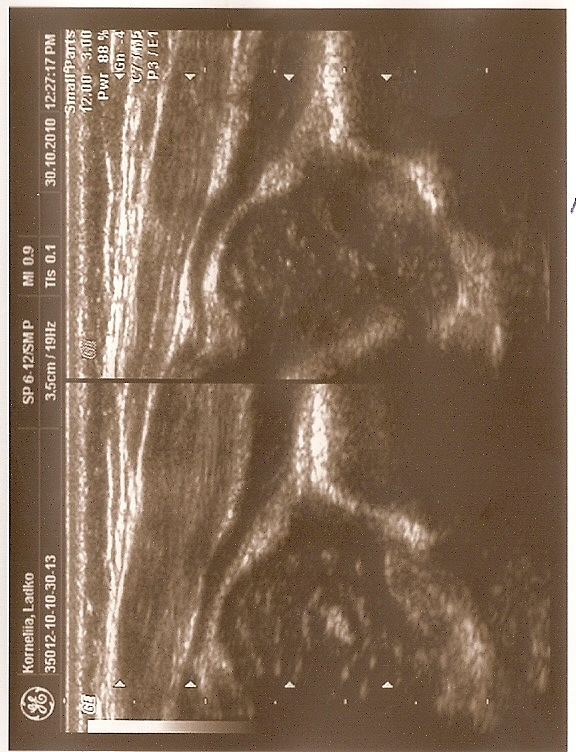

Type IIa+(GN coming to maturity) 6 weeks (below)

the bony roof satisfactory modeling

the bony rim angular but bony roof is only satisfactory ,the first part of bony roof is very good,but the second tail (deeper) is only satisfactory.

the cartilage roof cover the head;

the arrows show labrum (red) ;

the bony rim (yellow);

the lower iliac margin (blue) ,

the bony roof line (blue) is extends tangential to the lower iliac margin and tangent to the bony rim

the cartilage roof line(green) is drown tangential to the bony rim and through the middle point of the labrum echo;

asymmetry in the loose joint capsule; family DDH( when it occurs ask always about it)

the baseline (yellow) is drown parallel to ilium echo through the point of the junction of the perichondrium,the periosseum and ilium.

type I (abow) 6 weeks the bony roof is good

the bony rim blunt

the cartilage roof line(green) is drown tangential to the bony rim and through the middle point of the labrum echo ;

asymmetry in the loose joint capsule ,family DDH( when it occurs ask always about it)